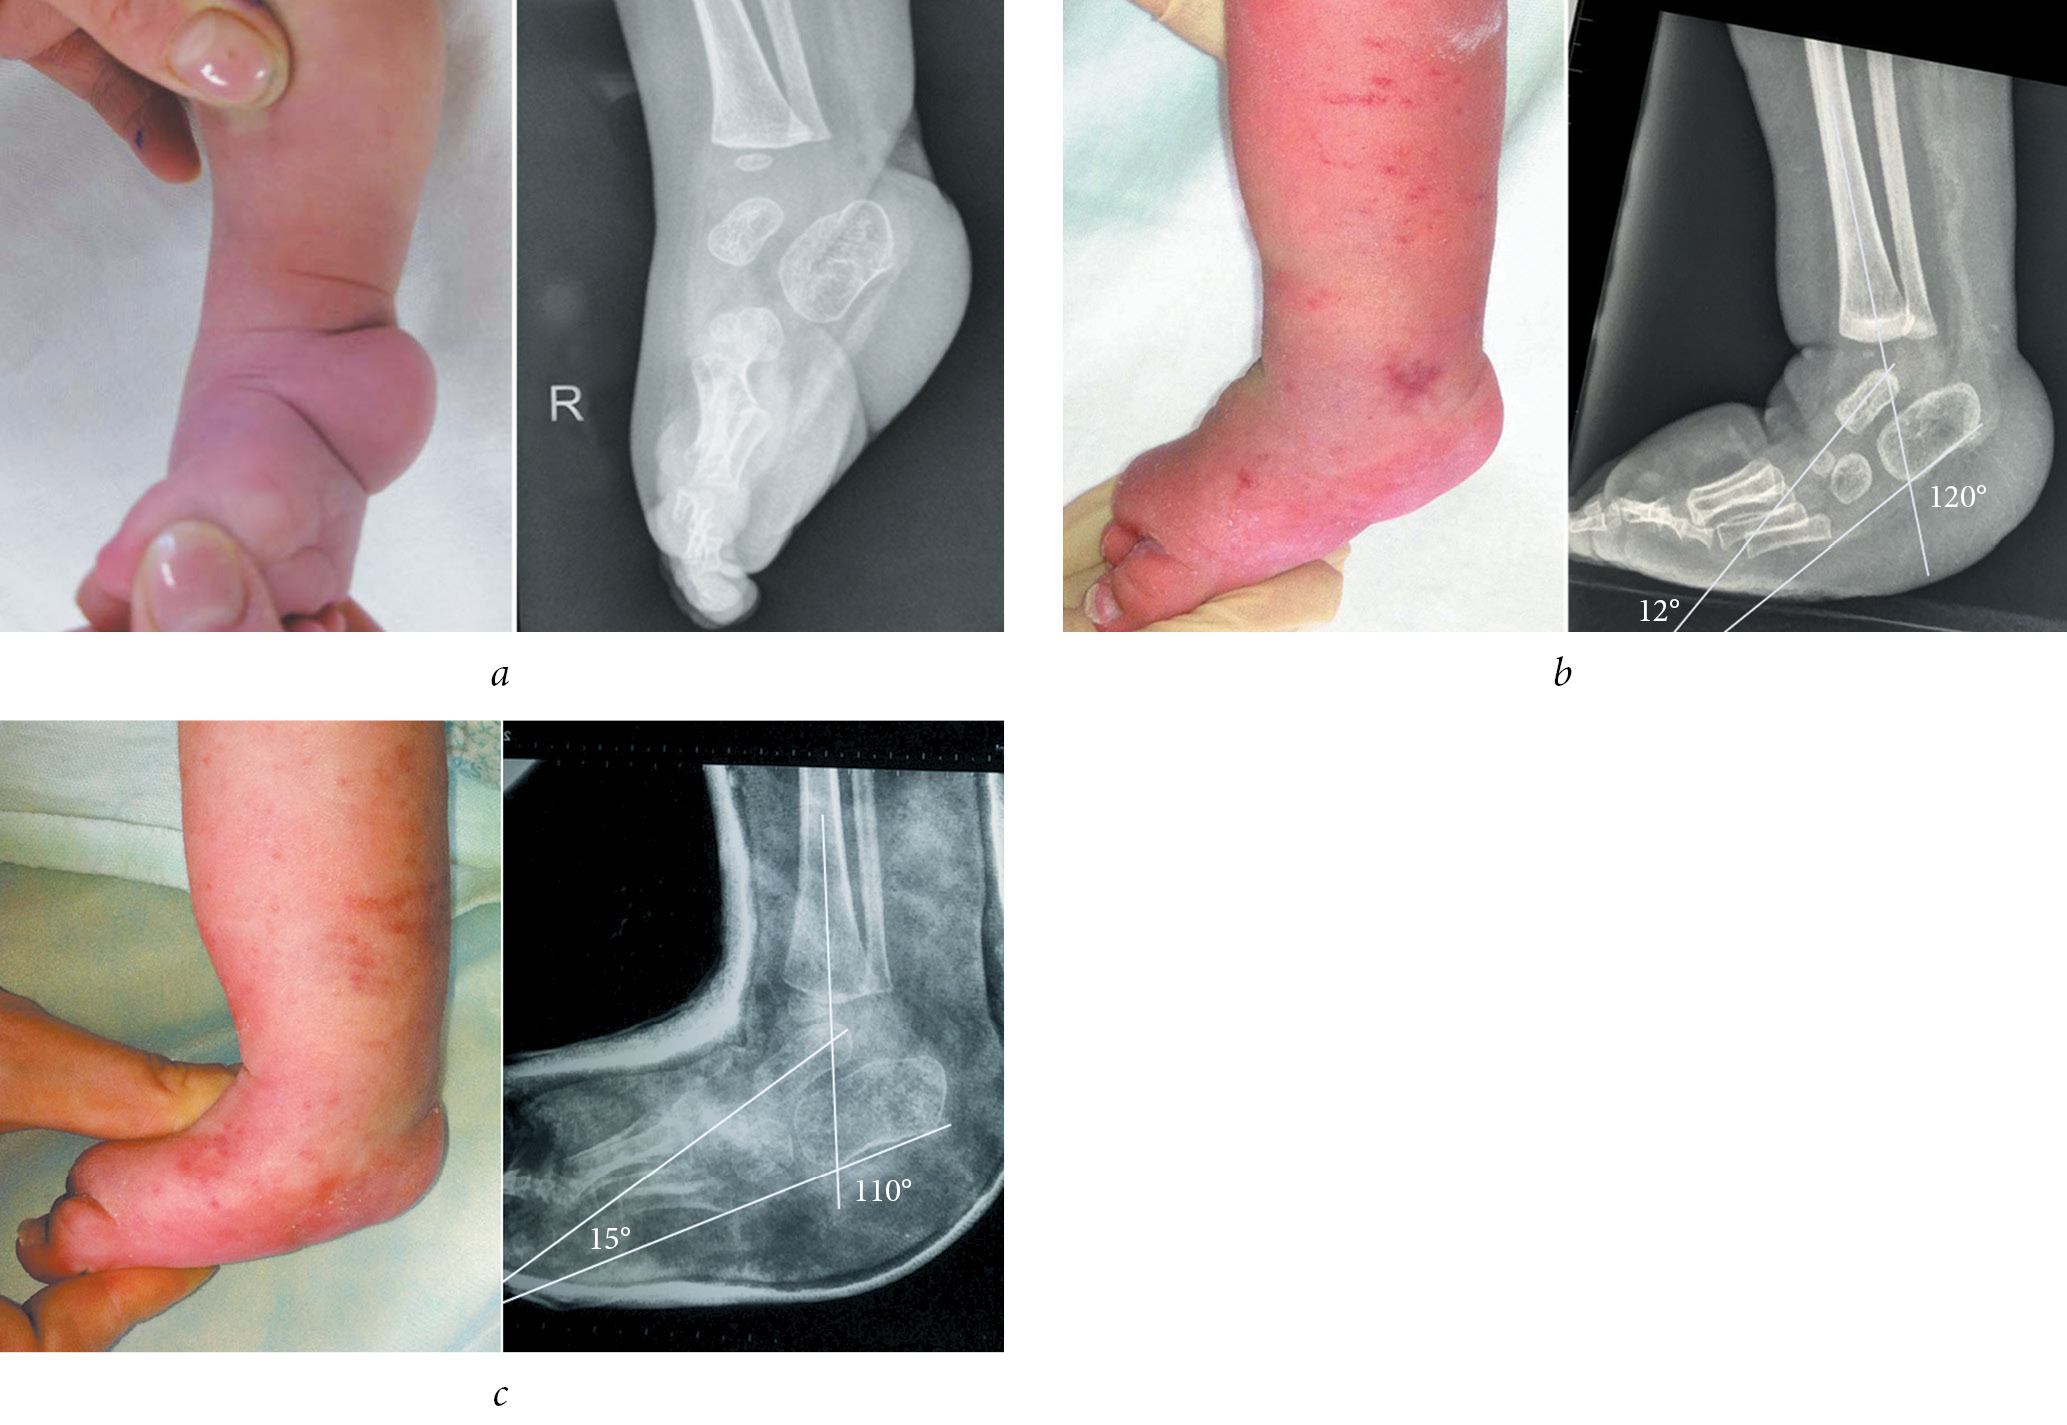

The illustration of some stages of treatment of patients of groups 1 and 2 with clubfoot with arthrogryposis according to the Ponseti method and radiographic data are presented in Figures 2 and 3.

Fig. 3. Appearance and radiograph of the foot in the lateral projection of patient M. with a clubfoot with arthrogryposis from group 2: a — before the beginning of Ponseti method of casting; b — before achillotomy; and c — after achillotomy